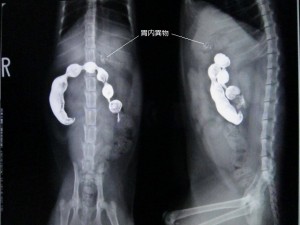

次の日のレントゲンです。

バリウムは結腸まで通貨していますが、胃内に不透過物が残っています。